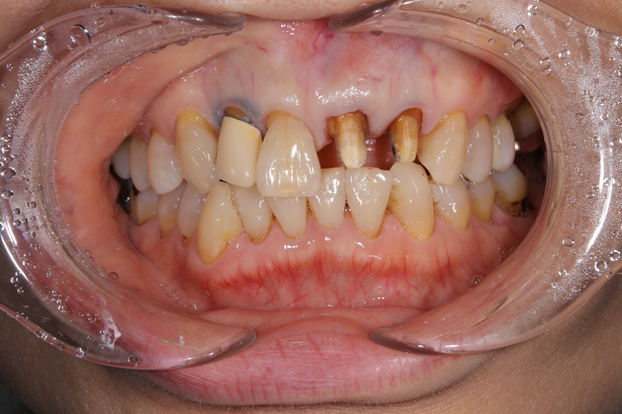

すでに被せ物を除去したあとの画像になりますが、歯を削ったところには保険のプラスチックの被せ物が入っていました。経年劣化でかなり黒ずんで見た目を悪くしていました。

歯の土台は特に大きな支障はなかったため、隣の前歯にしっかり色合わせが出来るセラミック治療を選択し説明した結果希望されました。